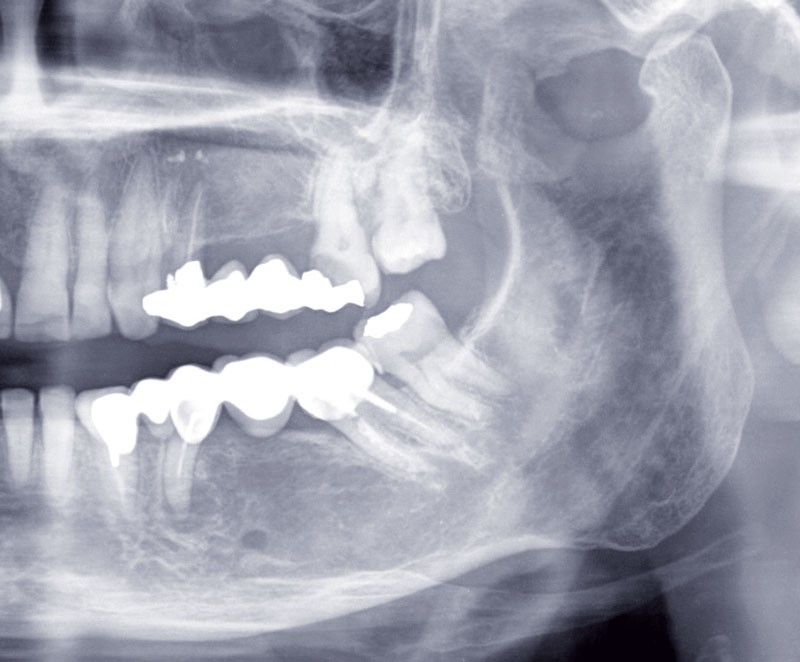

Au maxillaire, 3 implants Astra Tech Implant EV (Dentsply) sont posés en un temps chirurgical. Une empreinte pick-up sera réalisée après 4 mois de cicatrisation.